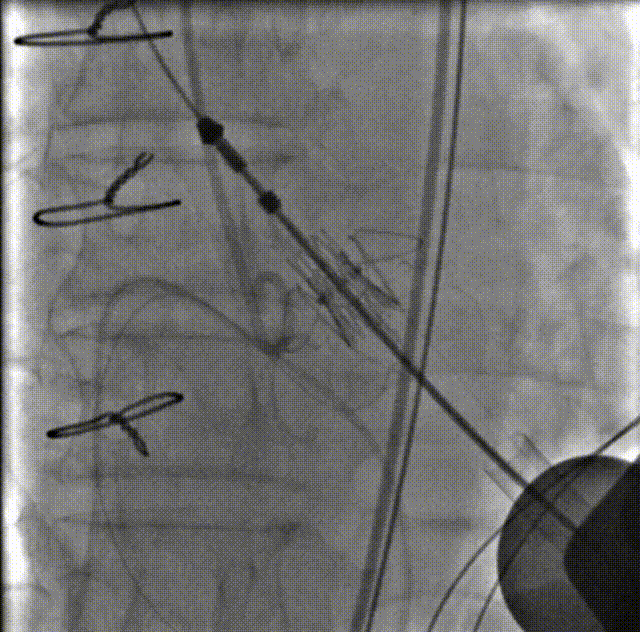

锁丝释放

第一个主动脉瓣锁丝释放后,瓣膜脱落进入主动脉。球囊拖瓣膜至降主动脉

二次瓣膜仓入位

瓣膜打开